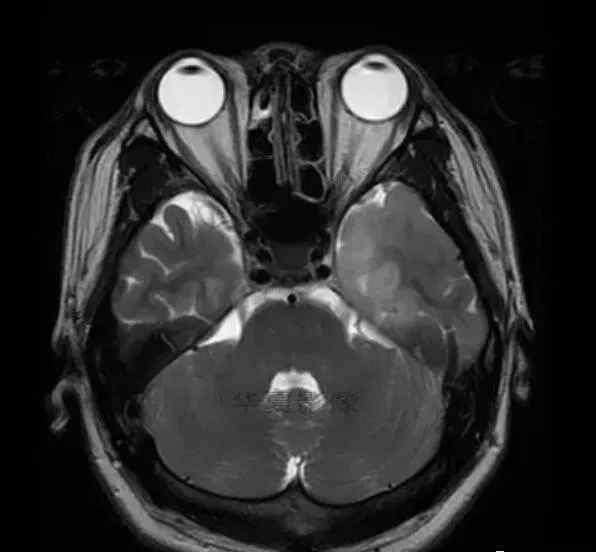

男,25岁,6天前意外感冒,现在发烧。他的体温超过39.0℃,他的呕吐物不是喷射状的。他的呕吐物是胃里的东西。

1.左侧颞叶、海马和岛叶T1WI信号低,T2WI信号高

2.病变没有明显的边界

3.占用效果不明显

4.豆状核不受影响